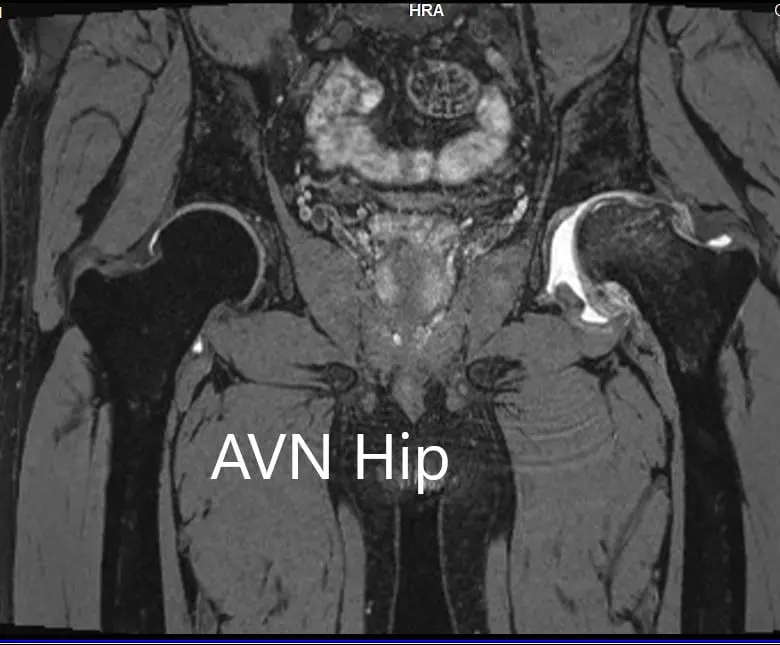

An MRI was obtained for diagnostic confirmation and staging of the disease. The left femoral head was collapsed with irregular contour and showed areas of altered signal intensity with a line of demarcation. Hypointense areas both on T1WI & T2WI seen in head suggestive of sclerosis. Surrounding marrow edema was seen

The left hip had advanced avascular necrosis with a collapse. The right hip was uninvolved presently. He was educated about the worsening collapse of the hip joint leading to his symptoms. Although the patient was young, he was advised a total hip replacement surgery in view of the collapse of the head of the femur with arthritis.